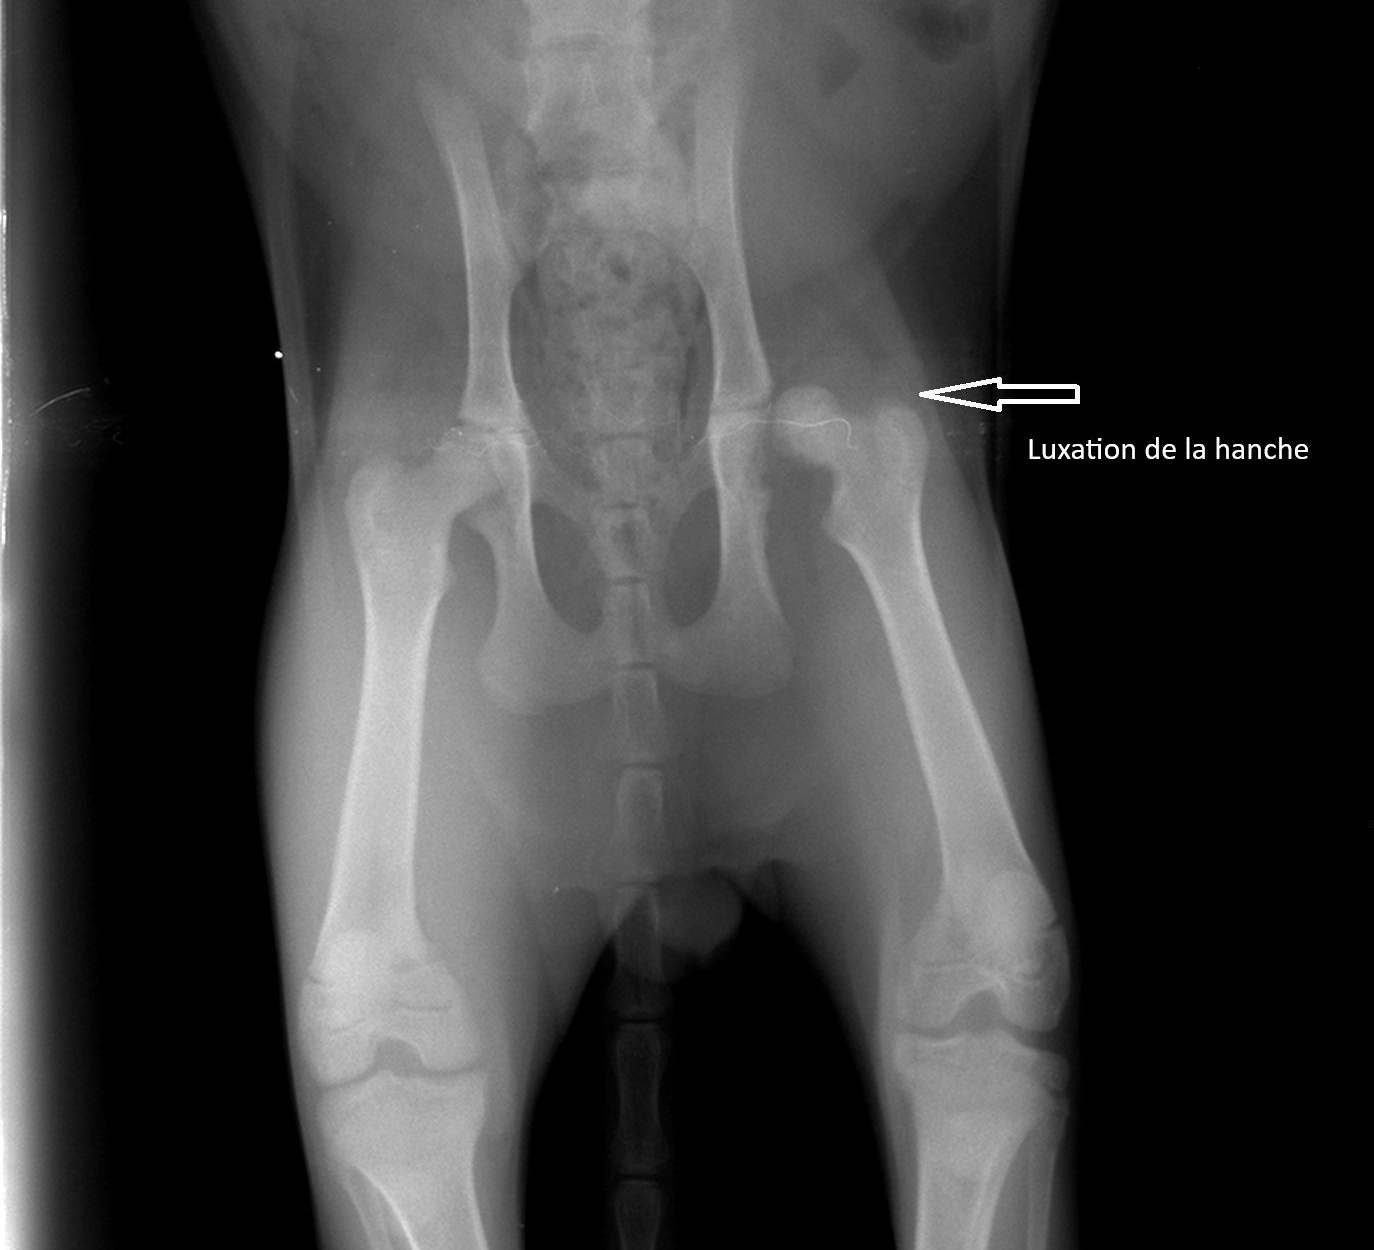

Dans la majorité des cas, l’origine est traumatique : une chute, un accident ou un choc violent peuvent provoquer une fracture ou une luxation de la hanche.

Plus rarement, la RTCF peut être indiquée en cas de malformation de la hanche, d’instabilité articulaire chronique ou d’arthrose avancée, lorsque l’usure progressive de l’articulation entraîne une gêne permanente.